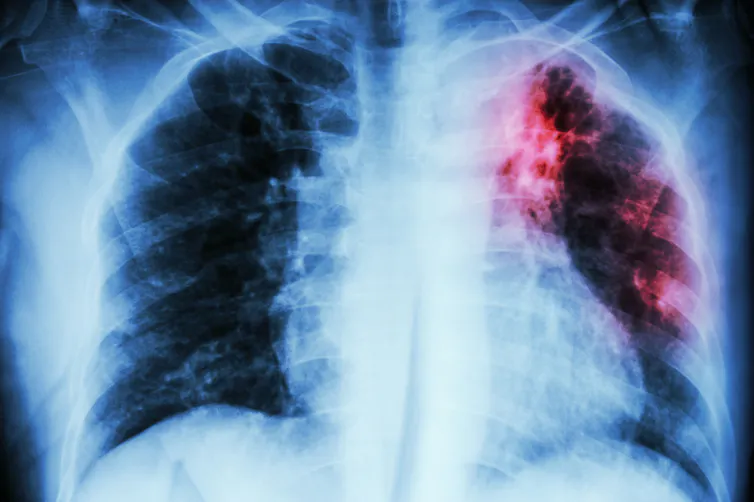

Tuberculosis typically infects the lungs but can spread to the rest of the body.

stockdevil/iStock via Getty Images Plus